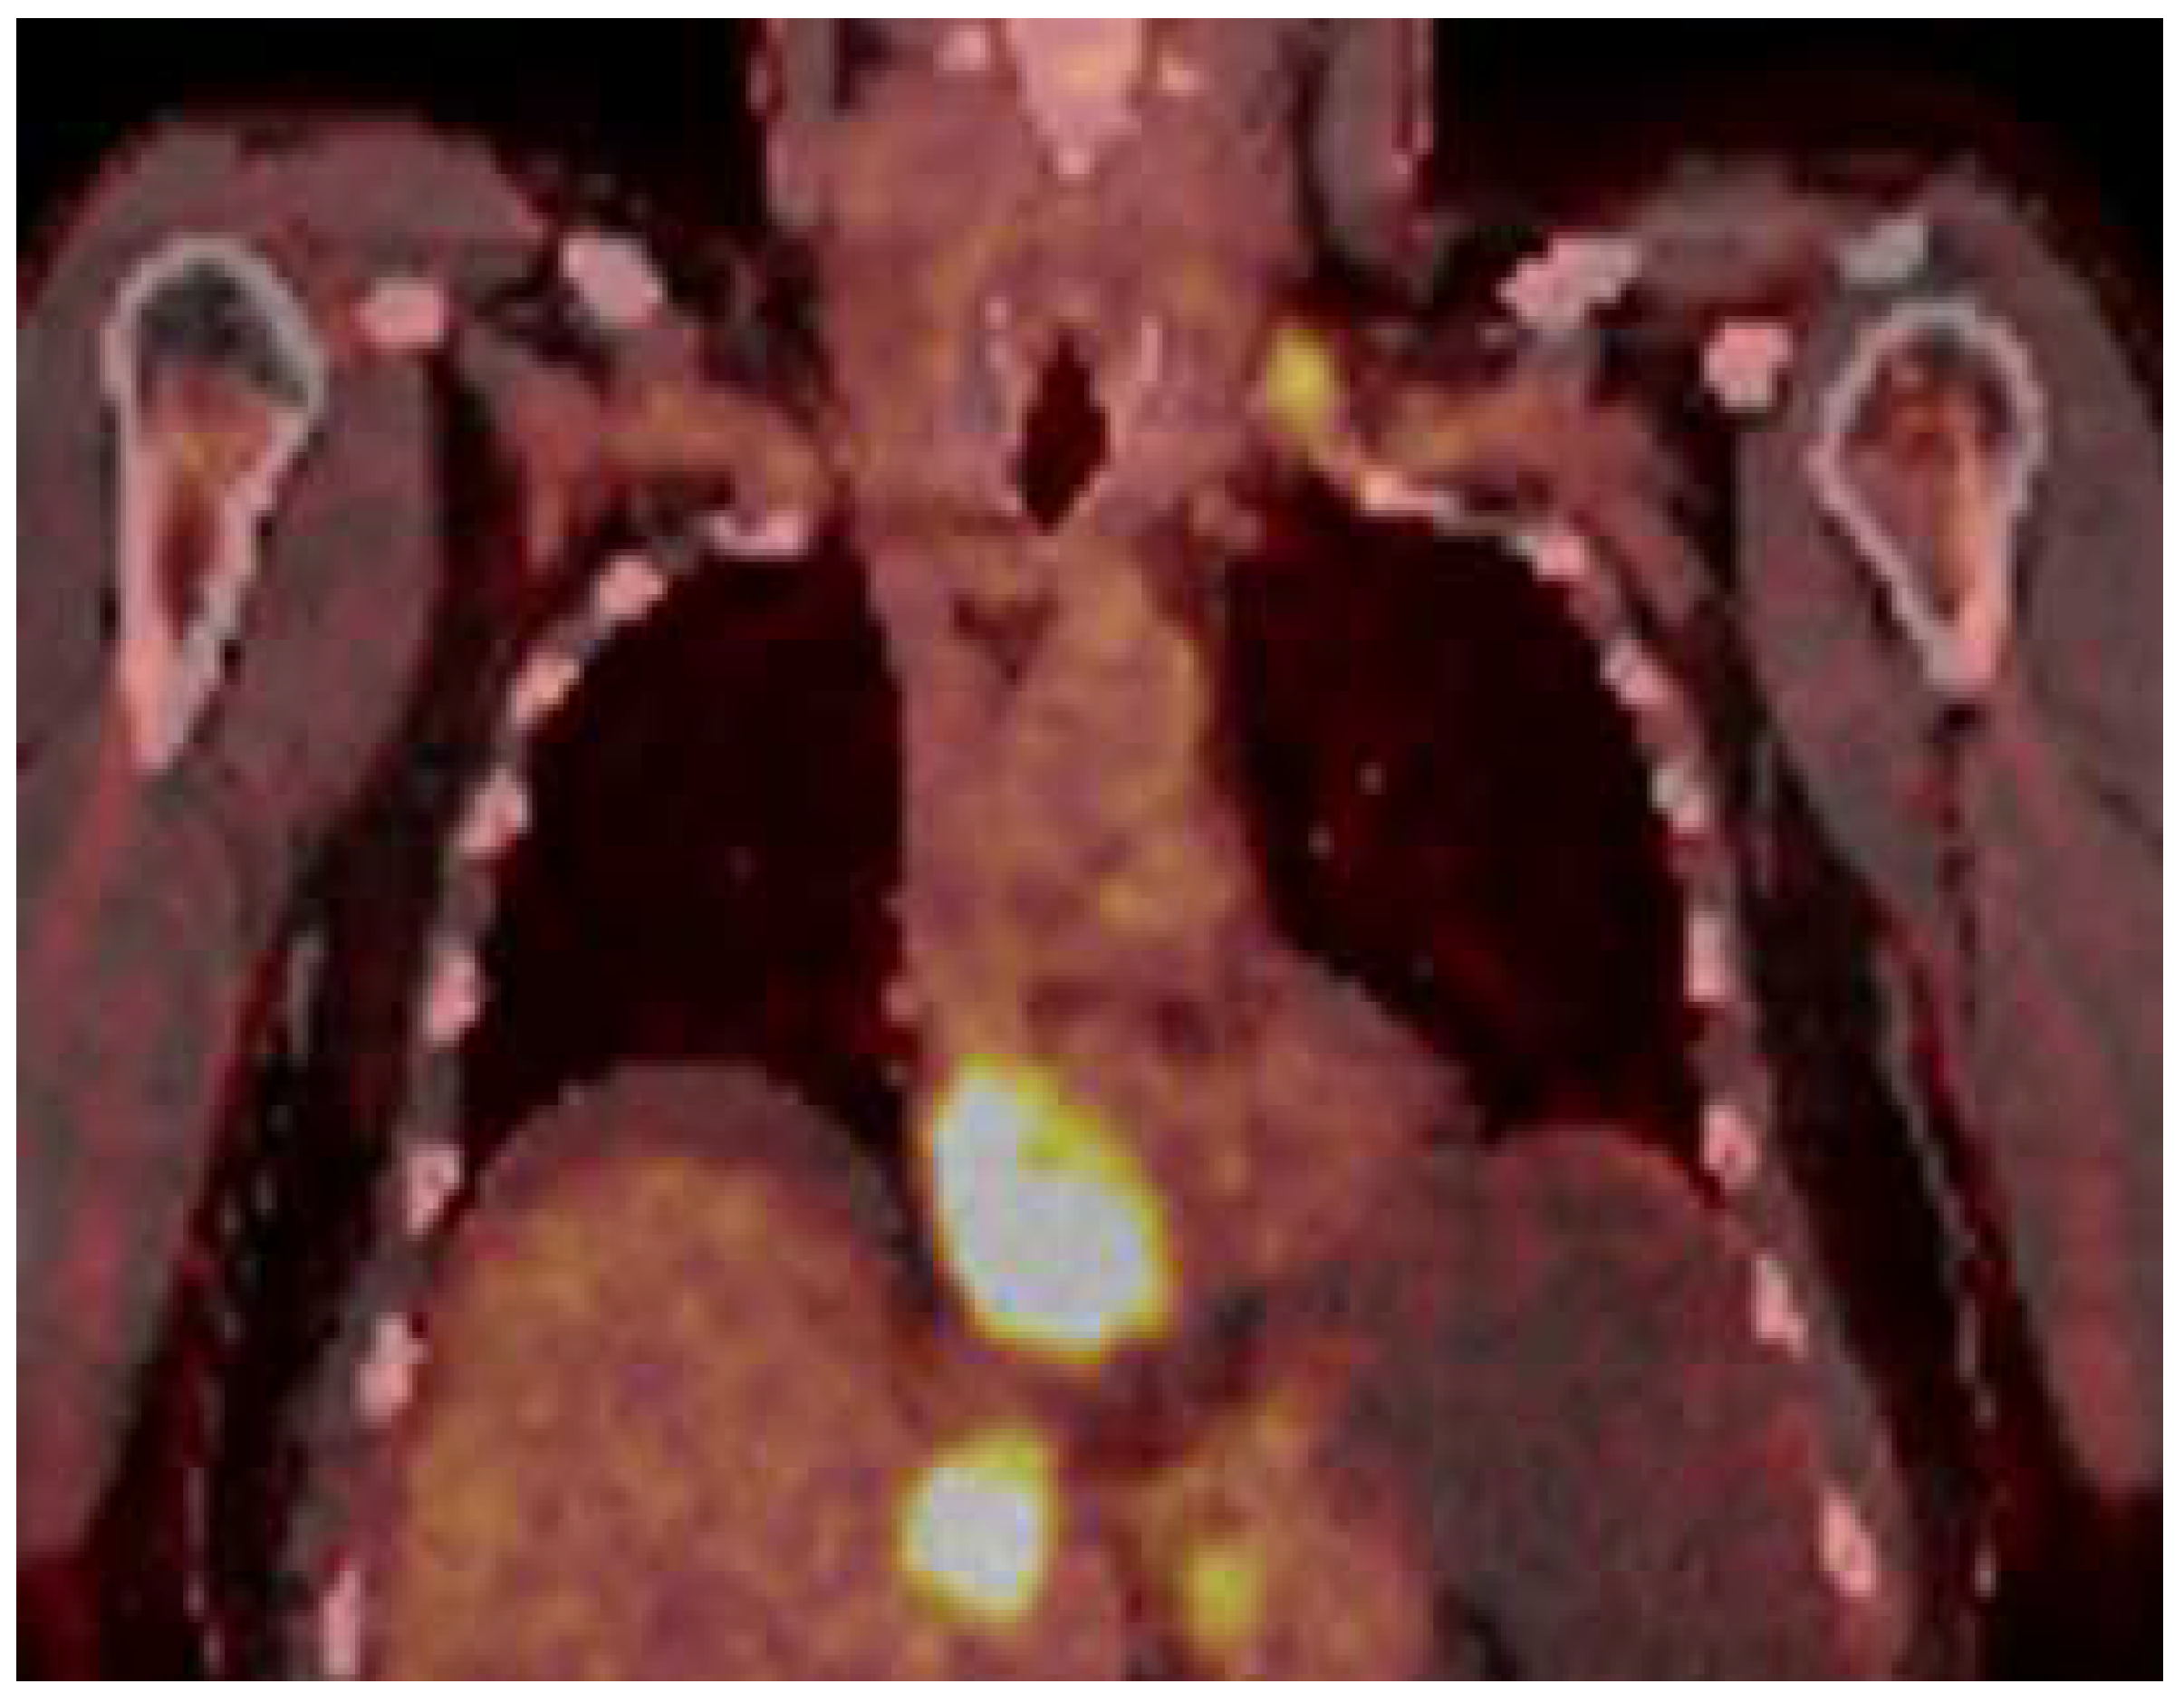

A 51-year-old male patient presented to our clinic in December 2023 with fatigue, abdominal distension and leg edema, which started three weeks prior. He had no history of chronic disease. On physical examination, dullness in the abdomen upon percussion, suggestive of fluid, was observed. Additionally, there were decreased breath sounds in the basals of the lungs, a tachycardic heart rhythm, and significant pretibial edema. The electrocardiogram (ECG) was consistent with sinus tachycardia. The patient’s blood pressure was 130/90 mmHg. Laboratory tests revealed hemoglobin: 13.2 g/dL; fasting blood glucose: 95 mg/dL; serum creatinine 1.2 mg/dL; aspartate aminotransferase (AST) 49 U/L; alanine aminotransferase (ALT): 46 U/L; bilirubin: 0.69 mg/dL; albumin: 3.6 g/dL; carcinoembryonic antigen (CEA): 43 ng/mL; and carbohydrate antigen (CA) 19-9: 361 U/mL. Electrolyte levels were within normal limits. Urinalysis showed proteinuria of 0.4 g/day. Paracentesis revealed a serum-to-ascites albumin gradient greater than 1.1 g/dL. Cytological examination of the fluid revealed benign cytological findings. TTE revealed a lesion 6.2 × 3.3 cm in diameter, suggestive of a low-moving hypoechoic thrombus or mass (Figure 1). This lesion almost completely filled the right atrium and stuck to the tricuspid valve. Dilation of the inferior vena cava and severe insufficiency of the tricuspid valve were also observed. A work-up was started to differentiate heart failure and a possible cardiac mass. Thorax CT showed multiple nodules in the lung and a suspicious mass in the right atrium. A PET scan showed that there was segmental wall thickening at the stomach and esophagogastric junction, measuring 7.5 cm in size and showing 18-FDG uptake with an SUV max of 22.4, which was evaluated in favor of primary malignancy. Multiple metastatic lymphadenopathy in the abdomen, free fluid in the abdominopelvic region, metastatic lesions in the liver and lung and supraclavicular lymphadenopathy were detected (Figure 2). The lesion seen on TTE was evaluated as a tumoral thrombus suspicious lesion with dimensions of 8.8 × 5.5 cm at the level of the right atrium on PET-CT and a maximum standard unit value (SUVmax) of 12.8. Cardiac magnetic resonance imaging (CMRI) was planned to differentiate the tumor/thrombus, but it could not be performed because the patient could not tolerate lying flat. Cardiology and surgery opinions were obtained, and close follow-up with anticoagulant treatment was recommended. An ulcerovegetating mass was detected in the upper-GI endoscopic evaluation. Histopathological evaluation of the biopsy specimen was consistent with gastric adenocarcinoma. PD-L1 IHC was conducted using a Ventana Dako anti-human PD-L1 mouse monoclonal antibody, clone 22C3, with a positive control. PD-L1 protein expression was assessed using the CPS and found to be positive, with a value of 15. HER-2 status was evaluated by both IHC and silver in situ hybridization (SISH). For IHC, Ventana anti-HER-2/neu rabbit monoclonal antibody clone: 4B5 was employed with a positive control. SISH was performed on a Ventana Benchmark Ultra fully automated system using the inform HER-2 dual in situ hybridization DNA probe cocktail with positive and negative controls. The HER-2 IHC score was +3, and SISH demonstrated HER-2 gene amplification with a HER-2/CEP17 ratio ≥ 2 (positive).

Figure 2. PET scan showed that there was a tumoral lesion with dimensions of 8.8 × 5.5 cm at the level of the right atrium with SUV max: 12.8.